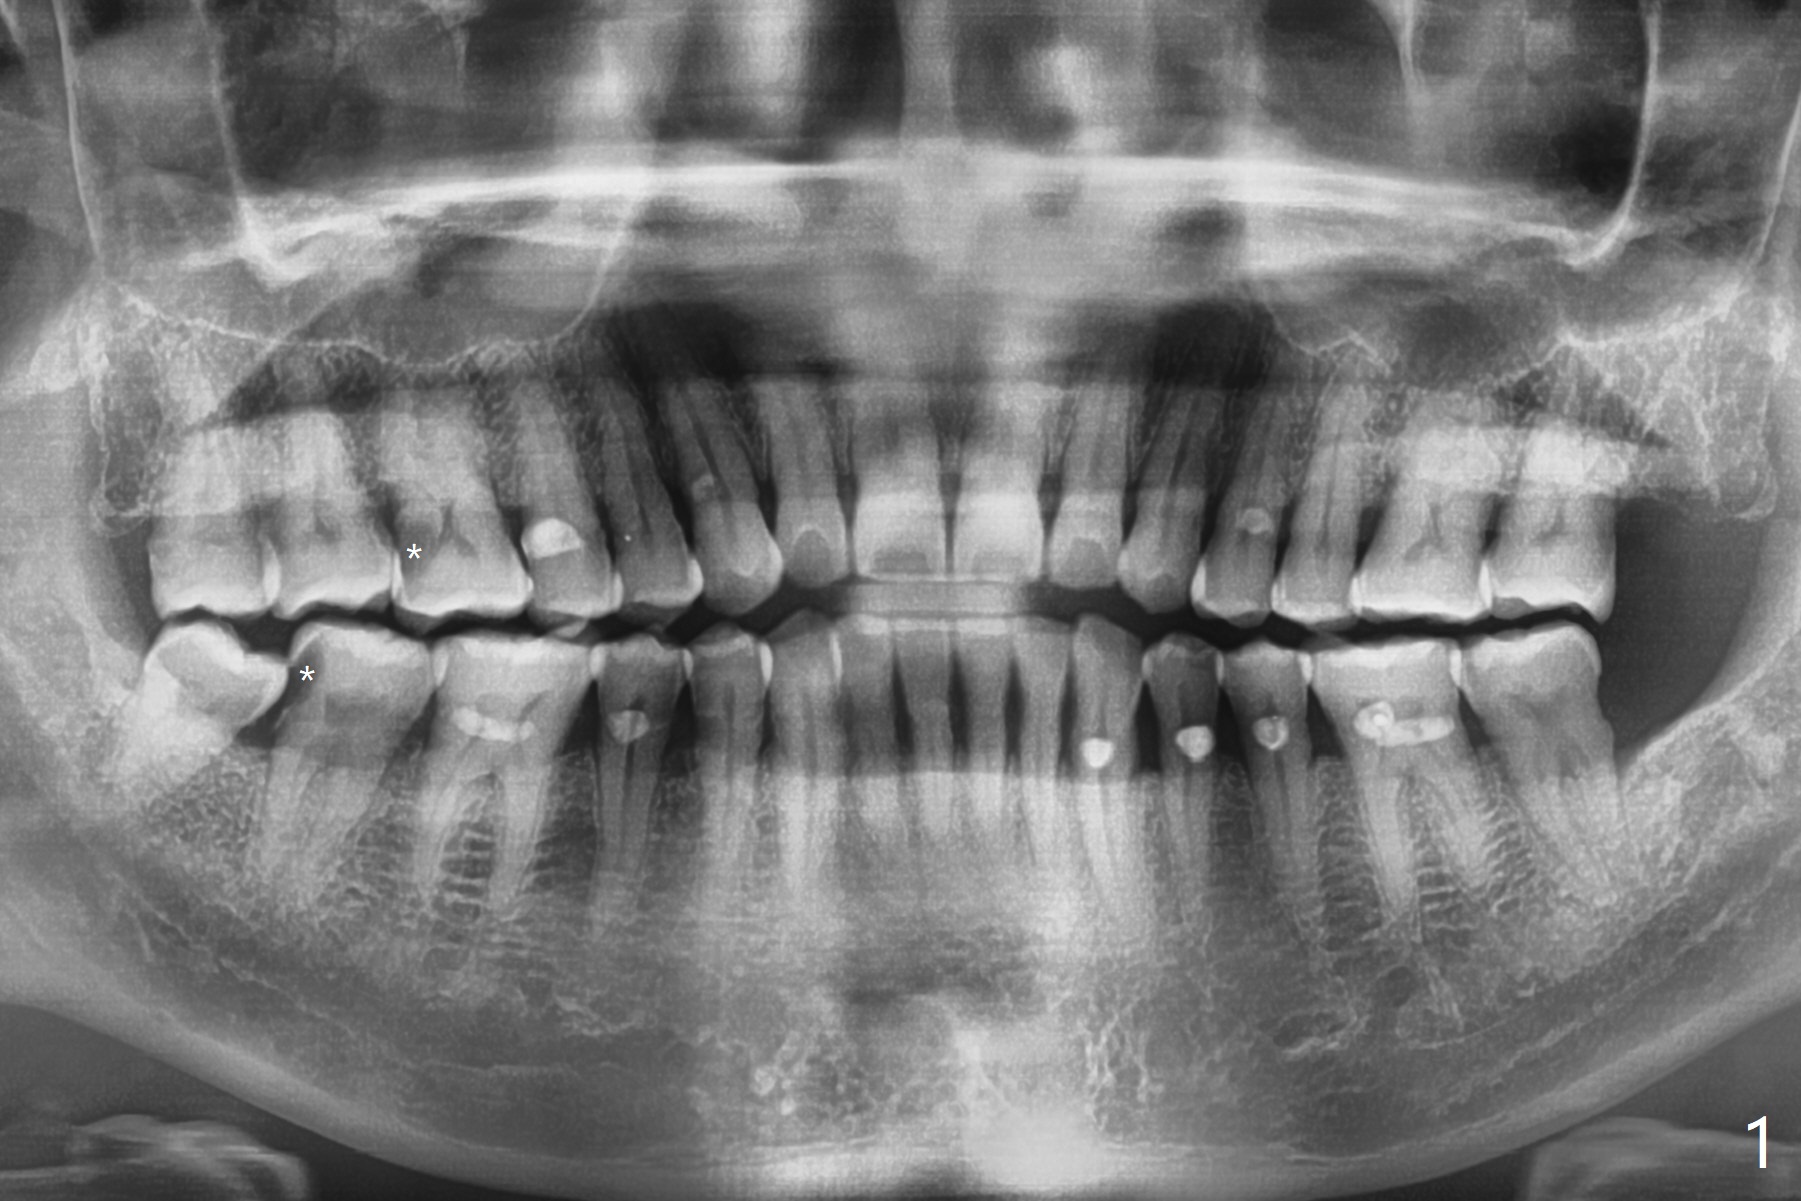

51岁男牙周炎,坚持他有蛀牙,全景片和根尖片显示右上第一右下第二磨牙远中龋(图一,二 *)。稍微分离右下智齿颊侧牙龈,分冠拔除,纱布塞入拔牙窝,好像第二磨牙远中龋去除比较容易,所以决定同期树脂修复。为了防止树脂脱落,去除龋坏后,在咬合面制备鸠尾。当时为了图省事,没有使用成型片,反而费时,尽管用纱布止血隔离,效果不好,徒手堆树脂不方便,尤其是牙龈处。下次必须用二号成型片,剪去近中牙龈部分,让远中部分完全入位,特别是牙龈缘。最后在拔牙窝放置胶原塞,缝合,防止干槽症。七天后缝线消失,伤口仿佛愈合,右下七没有症状。右上第一磨牙DO树脂修复,好像接近远中舌侧牙髓角,术后全景片(图三)似乎证实这一点。